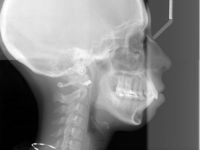

Phẫu thuật hàm và nâng mũi cùng lúc có an toàn không?

Cằm lẹm nên độn cằm hay phẫu thuật hàm?

Qua một vài bức ảnh tôi nhận thấy cằm tôi bị lẹm, vì vậy tôi bắt đầu tìm kiếm pp độn cằm. Càng nhìn vào cằm tôi càng nhận ra rằng đây có thể là kết quả của khớp thái dương hàm và có thể tôi sẽ cần phẫu thuật...

Nên phẫu thuật hàm hay niềng răng cho trường hợp hô vẩu, cười hở lợi

Tôi chuẩn bị niềng răng, dự tính hàm trên niềng răng mặt trong còn hàm dưới niềng răng mắc cài truyền thống. Một vài bác sĩ khuyên tôi nên phẫu thuật hàm nhưng cũng có 1 vài bác sĩ nói tôi chỉ cần nhổ 4 răng và...